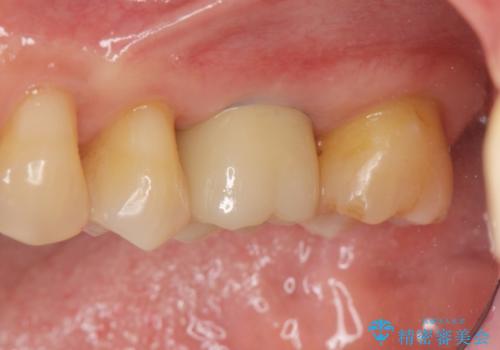

[遊離歯肉移植] インプラント周囲の角化歯肉の獲得

![[遊離歯肉移植] インプラント周囲の角化歯肉の獲得の症例 治療後](https://seimitsushinbi.jp/wp/wp-content/uploads/2020/01/f8e73ac6cf91eb450f830ba6ff08cd3a-500x350.jpg?v=1580303890)